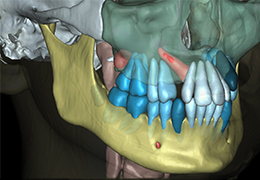

ANYTHINK 经导管主动脉瓣膜置换术分析系统